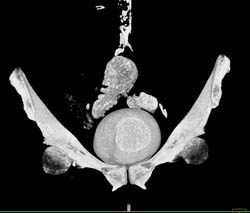

CT Cystogram With Fistulae to Colon